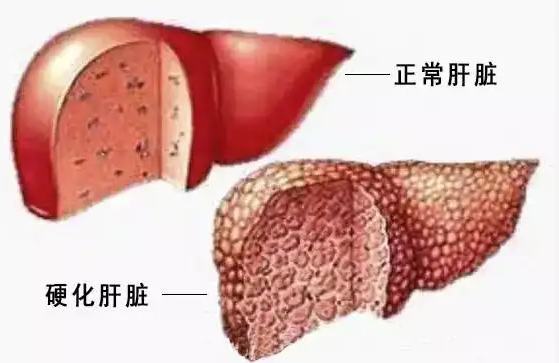

答:肝硬化,实际上我们在区分的时候,它就是有结节的,一般是看纤维化的程度,纤维化程度重的地方,会形成纤维结缔组织的集聚,形成结节。这个结节会有变化,它会增大,会融合,会癌变。

有的时候,要区别肝硬化结节和肝癌,还是挺难的,为什么呢?因为它可能是一个量变的过程到质变的过程,我们要想早期区别,是肝硬化的结节,还是一个早期的肝癌,确确实实还是有一定难度,不过我们现在也有一些办法,是可以做出一些早期判断的。